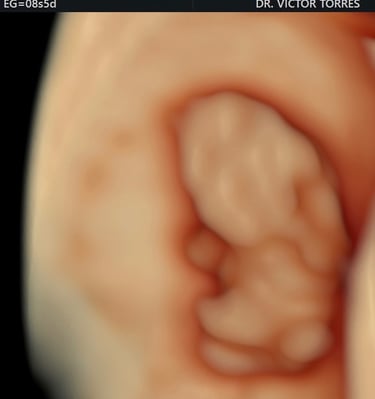

Monitoreo y cuidado especializado para el bienestar de tu bebé durante el embarazo.

Galería Neomamá

Explora momentos especiales y servicios para mamás y bebés aquí.